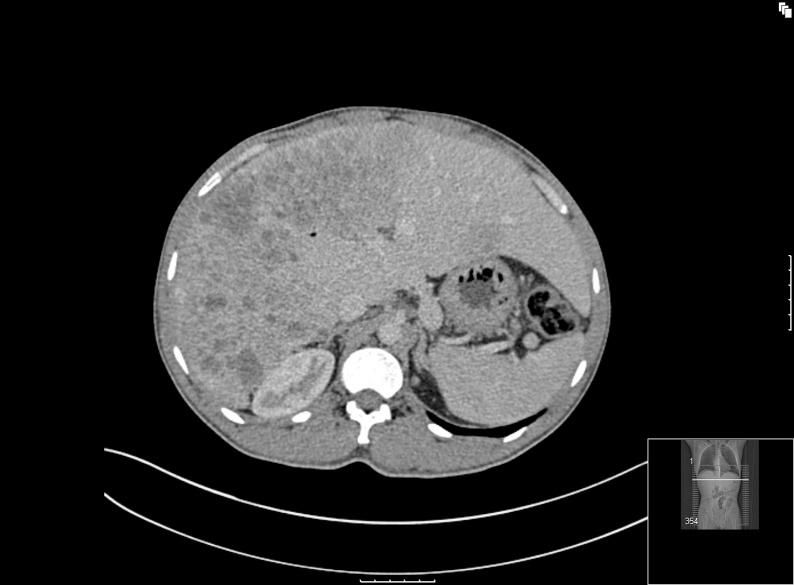

A 33-year-old male was diagnosed with a metastatic neuroendocrine carcinoma of uncertain primary. He defaulted from follow-up without therapy and some months later developed episodic severe hypoglycaemia, which was found to be associated with inappropriately elevated insulin and C-peptide levels. It was considered likely that the neuroendocrine tumour was the source of the insulin secretion. Diazoxide and somatostatin analogue were used to control hypoglycaemia. Much later in the course of the disease, he developed metabolic derangement, increased skin pigmentation and psychological disturbance, without frankly Cushingoid physical findings. Investigations revealed highly elevated cortisol levels (the levels having previously been normal) with markedly raised ACTH levels, consistent with the co-secretion of ACTH and insulin by the tumour. Treatment with metyrapone improved his psychological state and electrolyte imbalance. Unfortunately, despite several cycles of first-, second- and third-line chemotherapy from the start of the first hormonal presentation onwards, imaging revealed widespread progressive metastatic disease and the patient eventually passed away. This case highlights the importance of keeping in mind the biochemical heterogeneity of endocrine tumours during their treatment.

一名33岁男性被诊断为原发灶不明的转移性神经内分泌癌。他未接受治疗且未进行随访,数月后出现发作性严重低血糖,发现与胰岛素和C肽水平不适当升高有关。考虑神经内分泌肿瘤可能是胰岛素分泌的来源。使用二氮嗪和生长抑素类似物控制低血糖。在疾病过程的后期,他出现代谢紊乱、皮肤色素沉着增加和心理障碍,但无明显的库欣样体征。检查发现皮质醇水平显著升高(此前水平正常),促肾上腺皮质激素(ACTH)水平明显升高,这与肿瘤同时分泌ACTH和胰岛素一致。用甲吡酮治疗改善了他的心理状态和电解质失衡。不幸的是,从首次出现激素症状开始,尽管进行了几个周期的一线、二线和三线化疗,但影像学检查显示广泛进展性转移性疾病,患者最终去世。该病例强调了在治疗内分泌肿瘤时牢记其生化异质性的重要性。